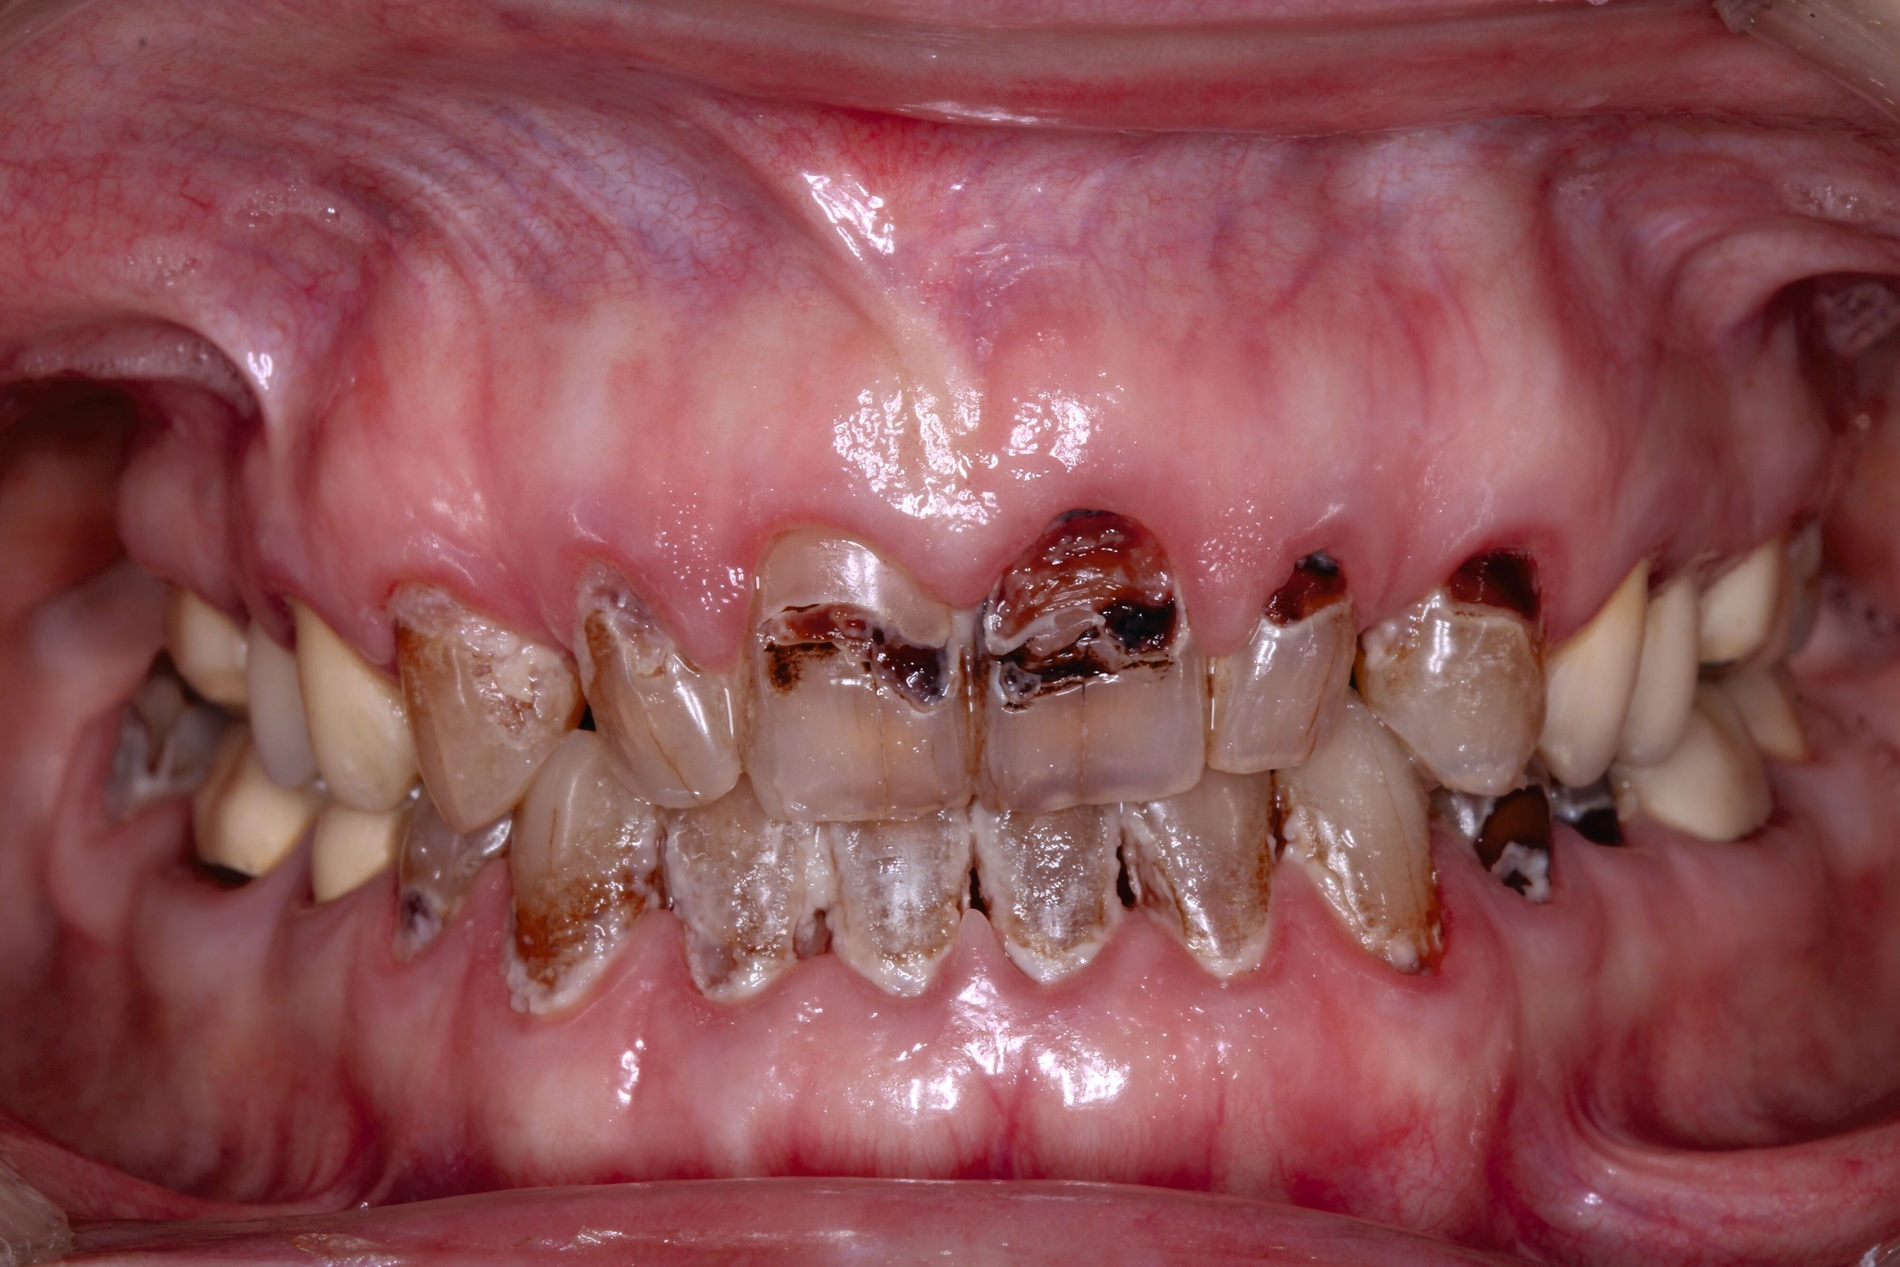

Zahnmedizinische Leitlinien zur zahnmedizinischen Betreuung von geriatrischen und demenziell erkrankten PatientInnen sind aktuell im Entstehungsprozess. Zusätzlich zu den oft komplexen zahnmedizinischen Befunden müssen bei der individuellen Therapieplanung dieser vulnerablen Klientel die Therapiefähigkeit und die Eigenverantwortlichkeit berücksichtigt werden. Dabei ist es weniger das Alter, sondern vielmehr der Zustand der körperlichen und mentalen Funktionsfähigkeit, der den Erfolg zahnmedizinischer Therapien limitiert. Therapien, die bei gesunden Personen jahrelang das Alltagsgeschäft der Zahnmedizin waren, sind bei Personen mit erhöhtem Pflege- und/oder Unterstützungsbedarf eventuell nicht umsetzbar. Gebrechlichkeit (Frailty) ist ein Zustand zwischen guter Gesundheit und Pflegebedürftigkeit im Alter – ein Zwischenstadium, in dem ein vorher fitter älterer Mensch Symptome der Gebrechlichkeit entwickelt und die Gefahr besteht, dass sich sein Zustand verschlechtert. Die geriatrischen Erkrankungen Frailty und auch Demenz sind im Rahmen zahnmedizinischer Behandlungen mit einer reduzierten Kooperations- und Therapiefähigkeit sowie bei der Anfertigung von Zahnersatz mit einer reduzierten Adaptationsfähigkeit assoziiert (Abbildung 3).